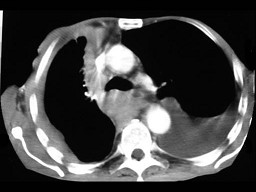

67岁,男,呼吸急促3个月,请结合胸片选出最可能的诊断()[WXJ-0111jpg]

A.包裹性胸腔积液

B.胸膜肥厚

C.化脓性胸膜炎

D.肺癌

E.胸膜间皮瘤

男,67岁,呼吸急促3月,结合胸片,最可能的诊断是()<img border="0" style="width: 302px; height: 226px;&quo

[单选题]男,67岁,呼吸急促3月,结合胸片,最可能的诊断是()A.包裹性胸腔积液B.胸膜肥厚C.化脓性胸膜炎D.肺癌E.胸膜间皮瘤

![67岁,男,呼吸急促3个月,请结合胸片选出最可能的诊断()[WXJ-0111jpg]<img style="width: 256px; height: 192px;" src 67岁,男,呼吸急促3个月,请结合胸片选出最可能的诊断()[WXJ-0111jpg]<img style="width: 256px; height: 192px;" src](https://img.zhaotiba.com/tiku58/11674609.jpg)